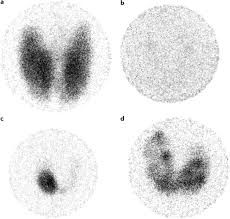

Graves Disease Nature Reviews Disease Primers